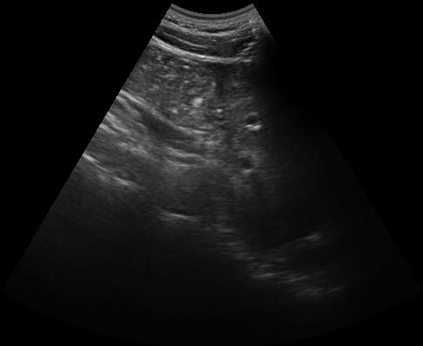

Most deep neural networks (DNNs) based ultrasound (US) medical image analysis models use pretrained backbones (e.g., ImageNet) for better model generalization. However, the domain gap between natural and medical images causes an inevitable performance bottleneck. To alleviate this problem, an US dataset named US-4 is constructed for direct pretraining on the same domain. It contains over 23,000 images from four US video sub-datasets. To learn robust features from US-4, we propose an US semi-supervised contrastive learning method, named USCL, for pretraining. In order to avoid high similarities between negative pairs as well as mine abundant visual features from limited US videos, USCL adopts a sample pair generation method to enrich the feature involved in a single step of contrastive optimization. Extensive experiments on several downstream tasks show the superiority of USCL pretraining against ImageNet pretraining and other state-of-the-art (SOTA) pretraining approaches. In particular, USCL pretrained backbone achieves fine-tuning accuracy of over 94% on POCUS dataset, which is 10% higher than 84% of the ImageNet pretrained model. The source codes of this work are available at https://github.com/983632847/USCL.